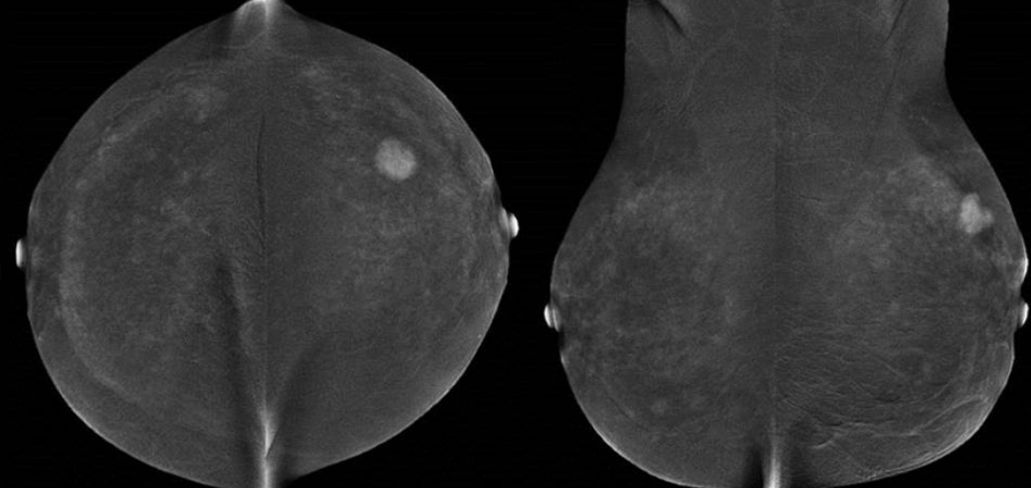

Kontrastmittel-Mammographie: Rekombinationsbild